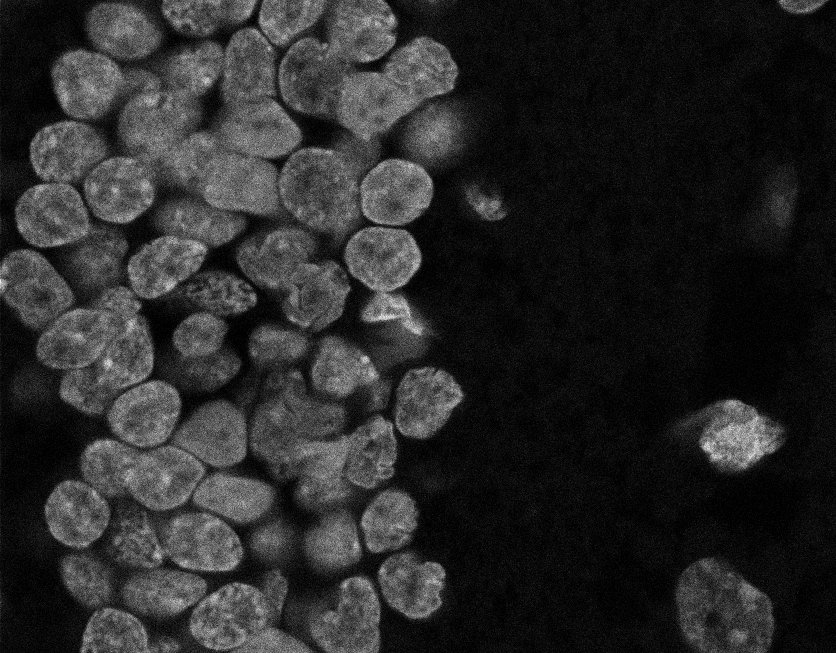

Nuclei

Nuclei - Bis

Nuclei - Bip

Nuclei - Bipolar